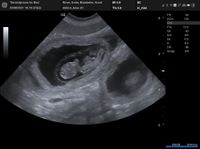

FANNY & MIKA sind stolze Eltern von 5 Puppies geworden.

VIGGO, VALETTA, VENIA, VIKA & VINNY

...und alle sind gesund.

Wir freuen uns sehr über unseren neuen Nachwuchs